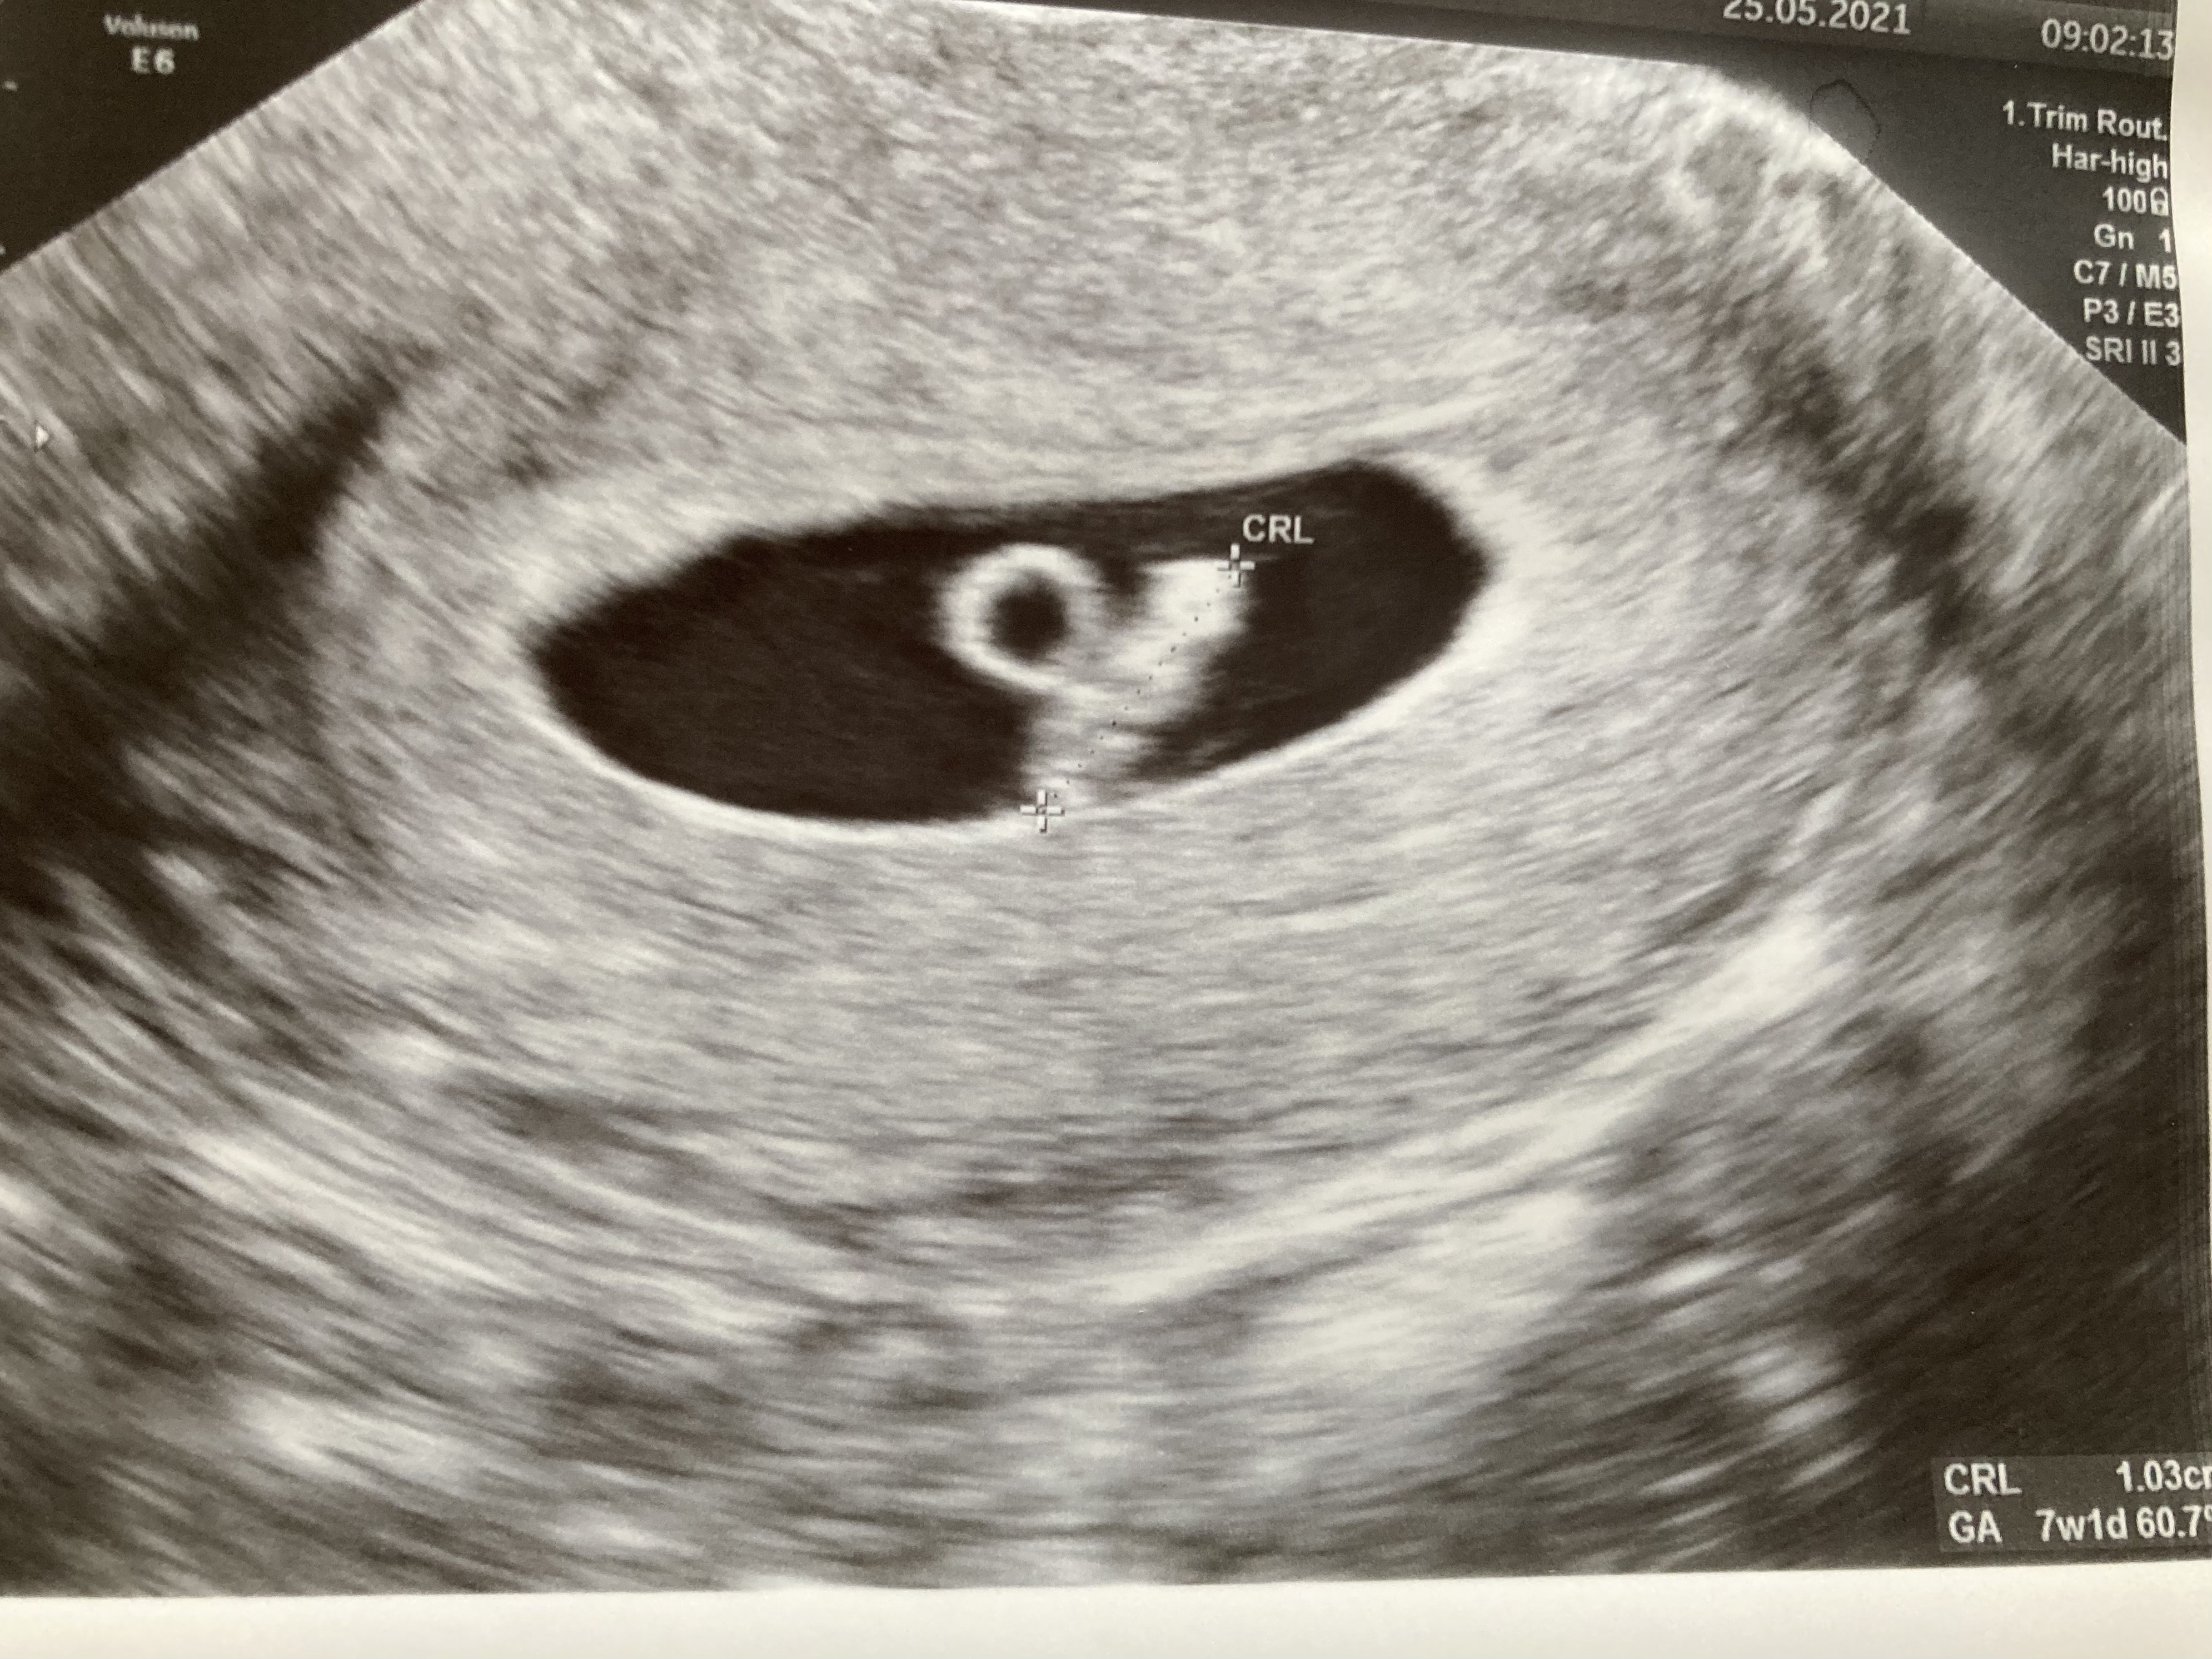

Melduję się po usg. Wczoraj próbowałam wrócić do pracy po l4, ale na wieczór znowu plamienie

Zarezerwowałam pierwszą wolną wizytę dziś - na szczęście wszystko jest ok, l4 przedłużone i mam leżeć. Załączam zdjęcie fasolki